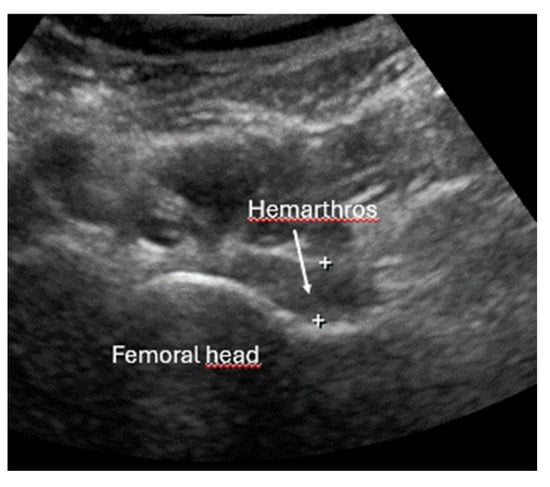

- Joint effusion and liphemarthrosis: fluid accumulation within a joint, sometimes containing fat droplets, which often indicates an intra-articular fracture.

- Example: Hemorrhagic Shock Due to Distal Femur Fracture—Rapid Diagnosis via Ultrasound